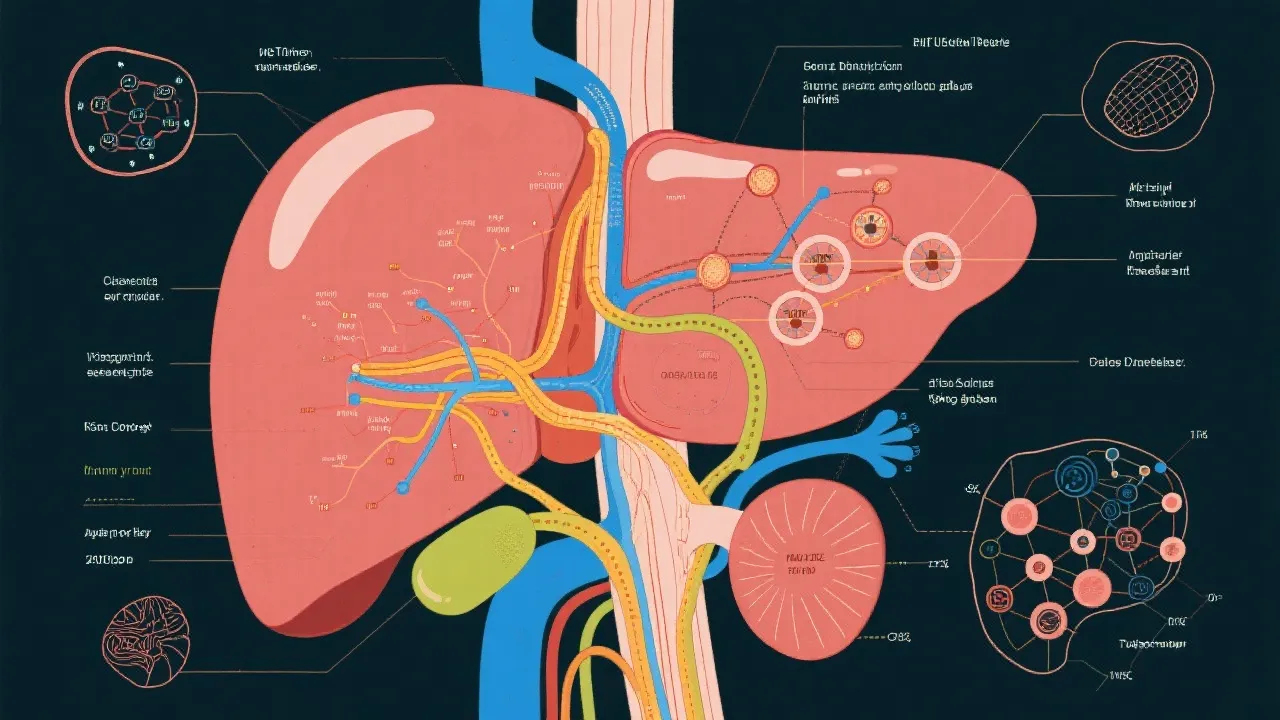

Cyp2e1 and Its Impact on NAFLD

Cyp2e1's Impact on NAFLD

Understanding Cyp2e1’s Role in NAFLD

The Role of Cyp2e1 in NAFLD

Cyp2e1's Role in NAFLD Understanding

Understanding Cyp2e1's Role in NAFLD

Understanding Cyp2e1 in NAFLD

Cyp2e1 and Nafld: A Molecular Connection

Cyp2e1 NAFLD: A Multifactorial Perspective

Cyp2e1 Role in Nafld

Understanding Cyp2e1's Role in NAFLD

Cyp2e1's Role in NAFLD

Understanding Hepatitis E and Liver Transplant

Understanding Hepatitis E and Liver Transplants

Understanding Hepatitis E and Liver Transplants

Understanding Hepatitis E and Liver Transplants

Understanding Hepatitis E and Liver Transplants

Hepatitis E and Liver Transplant

Understanding Hepatitis E and Liver Transplant

Understanding Hepatitis E and Liver Transplants

Navigating Hepatitis E and Liver Transplant

Navigating Hepatitis E Liver Transplants

Hepatitis E and Liver Transplant Insights

Hepatitis E and Liver Transplant